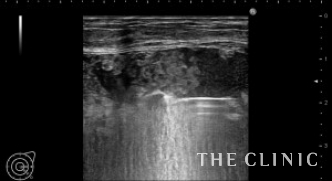

左)エコー下にベイザーリポで充実性成分を崩します。